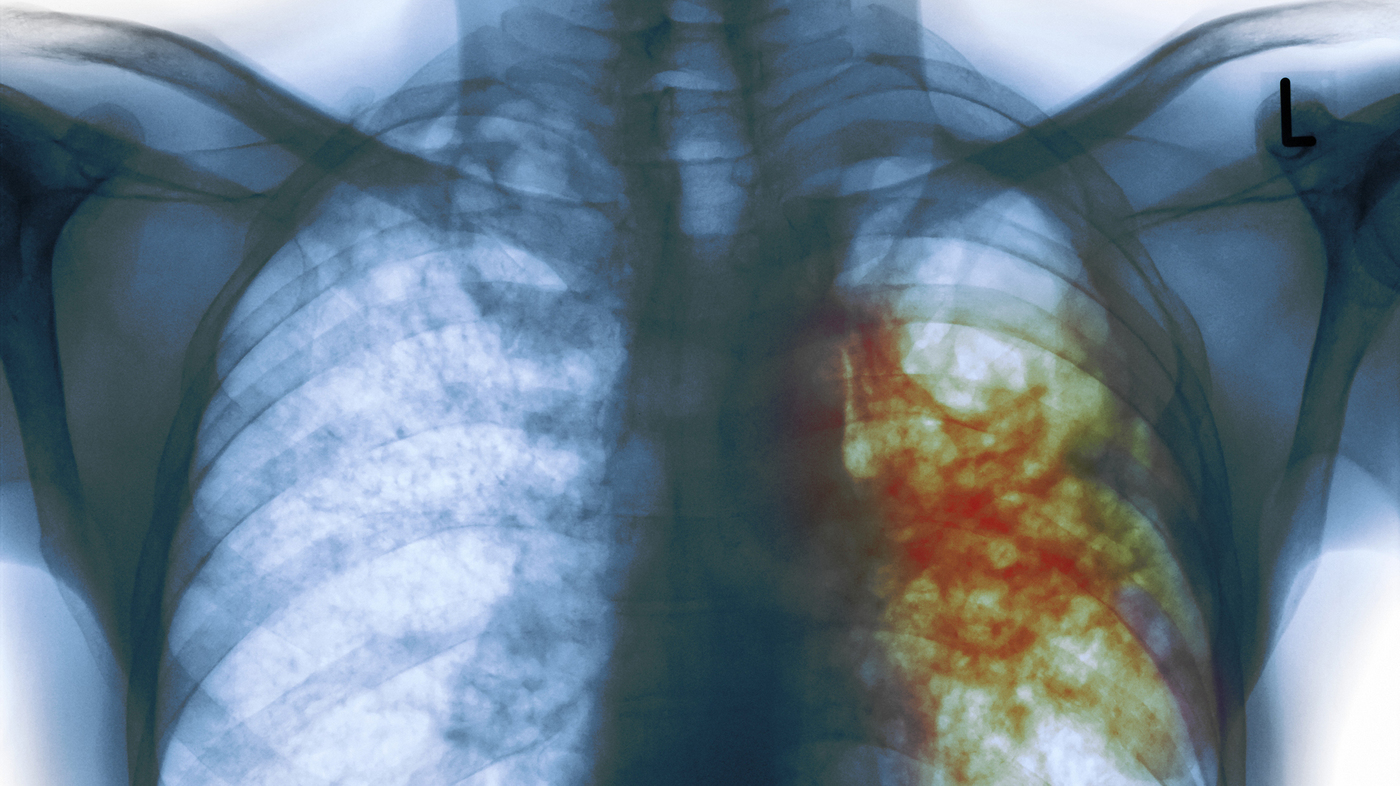

ΦΥΜΑΤΙΩΣΗ

Διεγνώσθη με φυματίωση ο Λούκας Πέρεθ – Φόβοι για διασπορά στα αποδυτήρια της Αϊντχόφεν

Ανησυχία ΠΟΥ για αύξηση κρουσμάτων φυματίωσης σε παιδιά

BINTEO: Επιστρέφει ο "εφιάλτης" της φυματίωσης;

Κρούει τον κώδωνα του κινδύνου ο Παγκόσμιος Οργανισμός Υγείας

Αύξηση των θανάτων από φυματίωση καταγράφεται για πρώτη φορά εδώ και δέκα χρόνια

Εξαιτίας της δυσχερής πρόσβαση των ασθενών στις δομές υγείας και